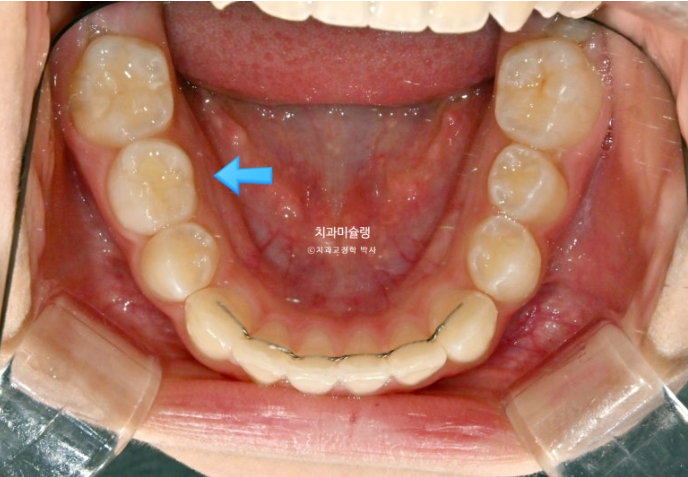

24.02

파란 화살표의 튀어나온 부분을 wing 이라고 부릅니다.

날개같이 생겼기 때문입니다.

위, 아래 장치에 총 4개의 Wing이 불어 나오며 이 Wing 때문에 아래턱을 내밀어 무는 위치로 유도가 됩니다.

근기능장치의 원리는 쉽게 말해 정상 위치에 턱이 적응하게 함으로써 실제로 아래턱뼈가 자라게 해주는 것 이라고 할 수 있겠습니다.